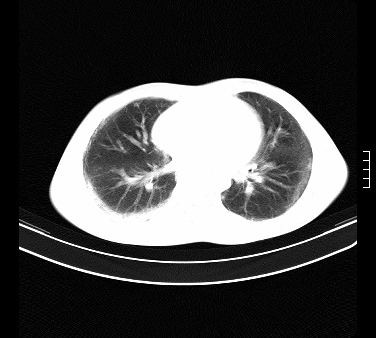

患者,男,17岁,系我院急诊科收治的一例百草枯中毒患者,做ct检查时,距离服药的时间为3天。上传与大家分享

补充:百草枯进入人体内主要分部于肺和骨骼,肺部损伤24小时内出现水肿,2-3天内出现急性呼吸窘迫综合征,1-2周内出现肺纤维化。(引自陈灏珠,实用内科学12版)